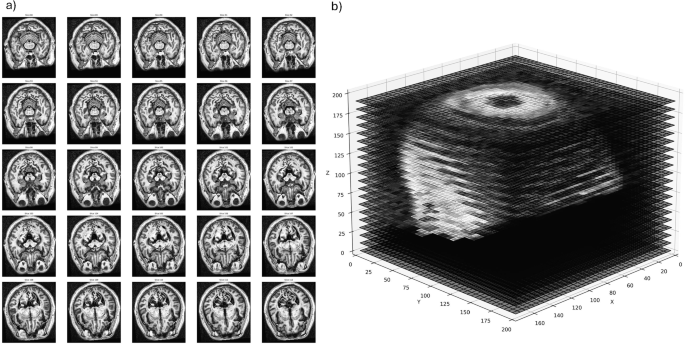

Figure 1 illustrates the preprocessing outcomes: (a) exemplar midline slices used in 2D analysis, demonstrating consistent midbrain positioning, and (b) 3D volume visualization showing preserved structural relationships across the brain.

a Example of single slices centered on the midbrain used individually to classify between PD and HC in the two-dimensional analyses. b Entire volumetric MRI scan used in the three-dimensional analyses. Gaps are inserted at regular intervals to help visualize the inner structure, but are not implemented in the analyses.